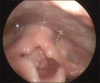

Recurrent respiratory papillomatosis (RRP) is a rare, chronic disease of viral etiology affecting most commonly larynx. A 5-year-old child with stridor was posted for microlaryngoscopic excision of laryngeal papilloma. We discuss the perioperative management of case with the various ventilation strategies. In child with stridor intubation remains the safest option. It is suggested to maintain spontaneous ventilation until intubation as mask ventilation could be difficult.